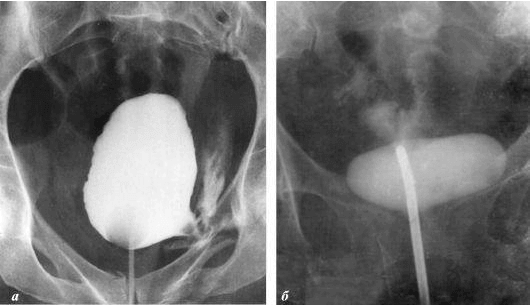

+ Vedere le immagini (18+)

interesting image

Cancro alla prostata in un uomo di 58 anni.

La stasi provoca il deposito di colesterolo sulle pareti dei vasi sanguigni, il che può comportare il restringimento del loro lume e alla formazione di microtrombi. Questo peggiora la nutrizione della ghiandola prostatica e contribuisce allo sviluppo dell’infiammazione in essa.